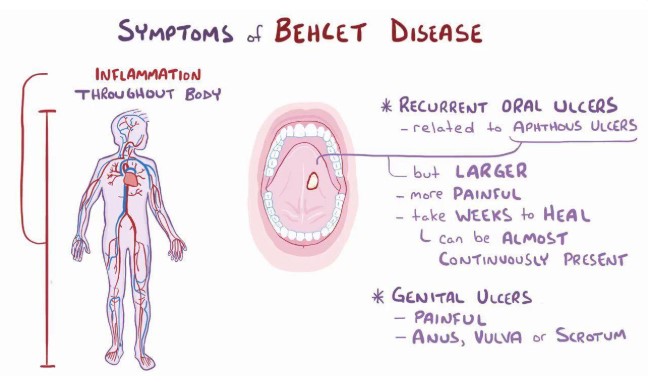

کیت های عفونی